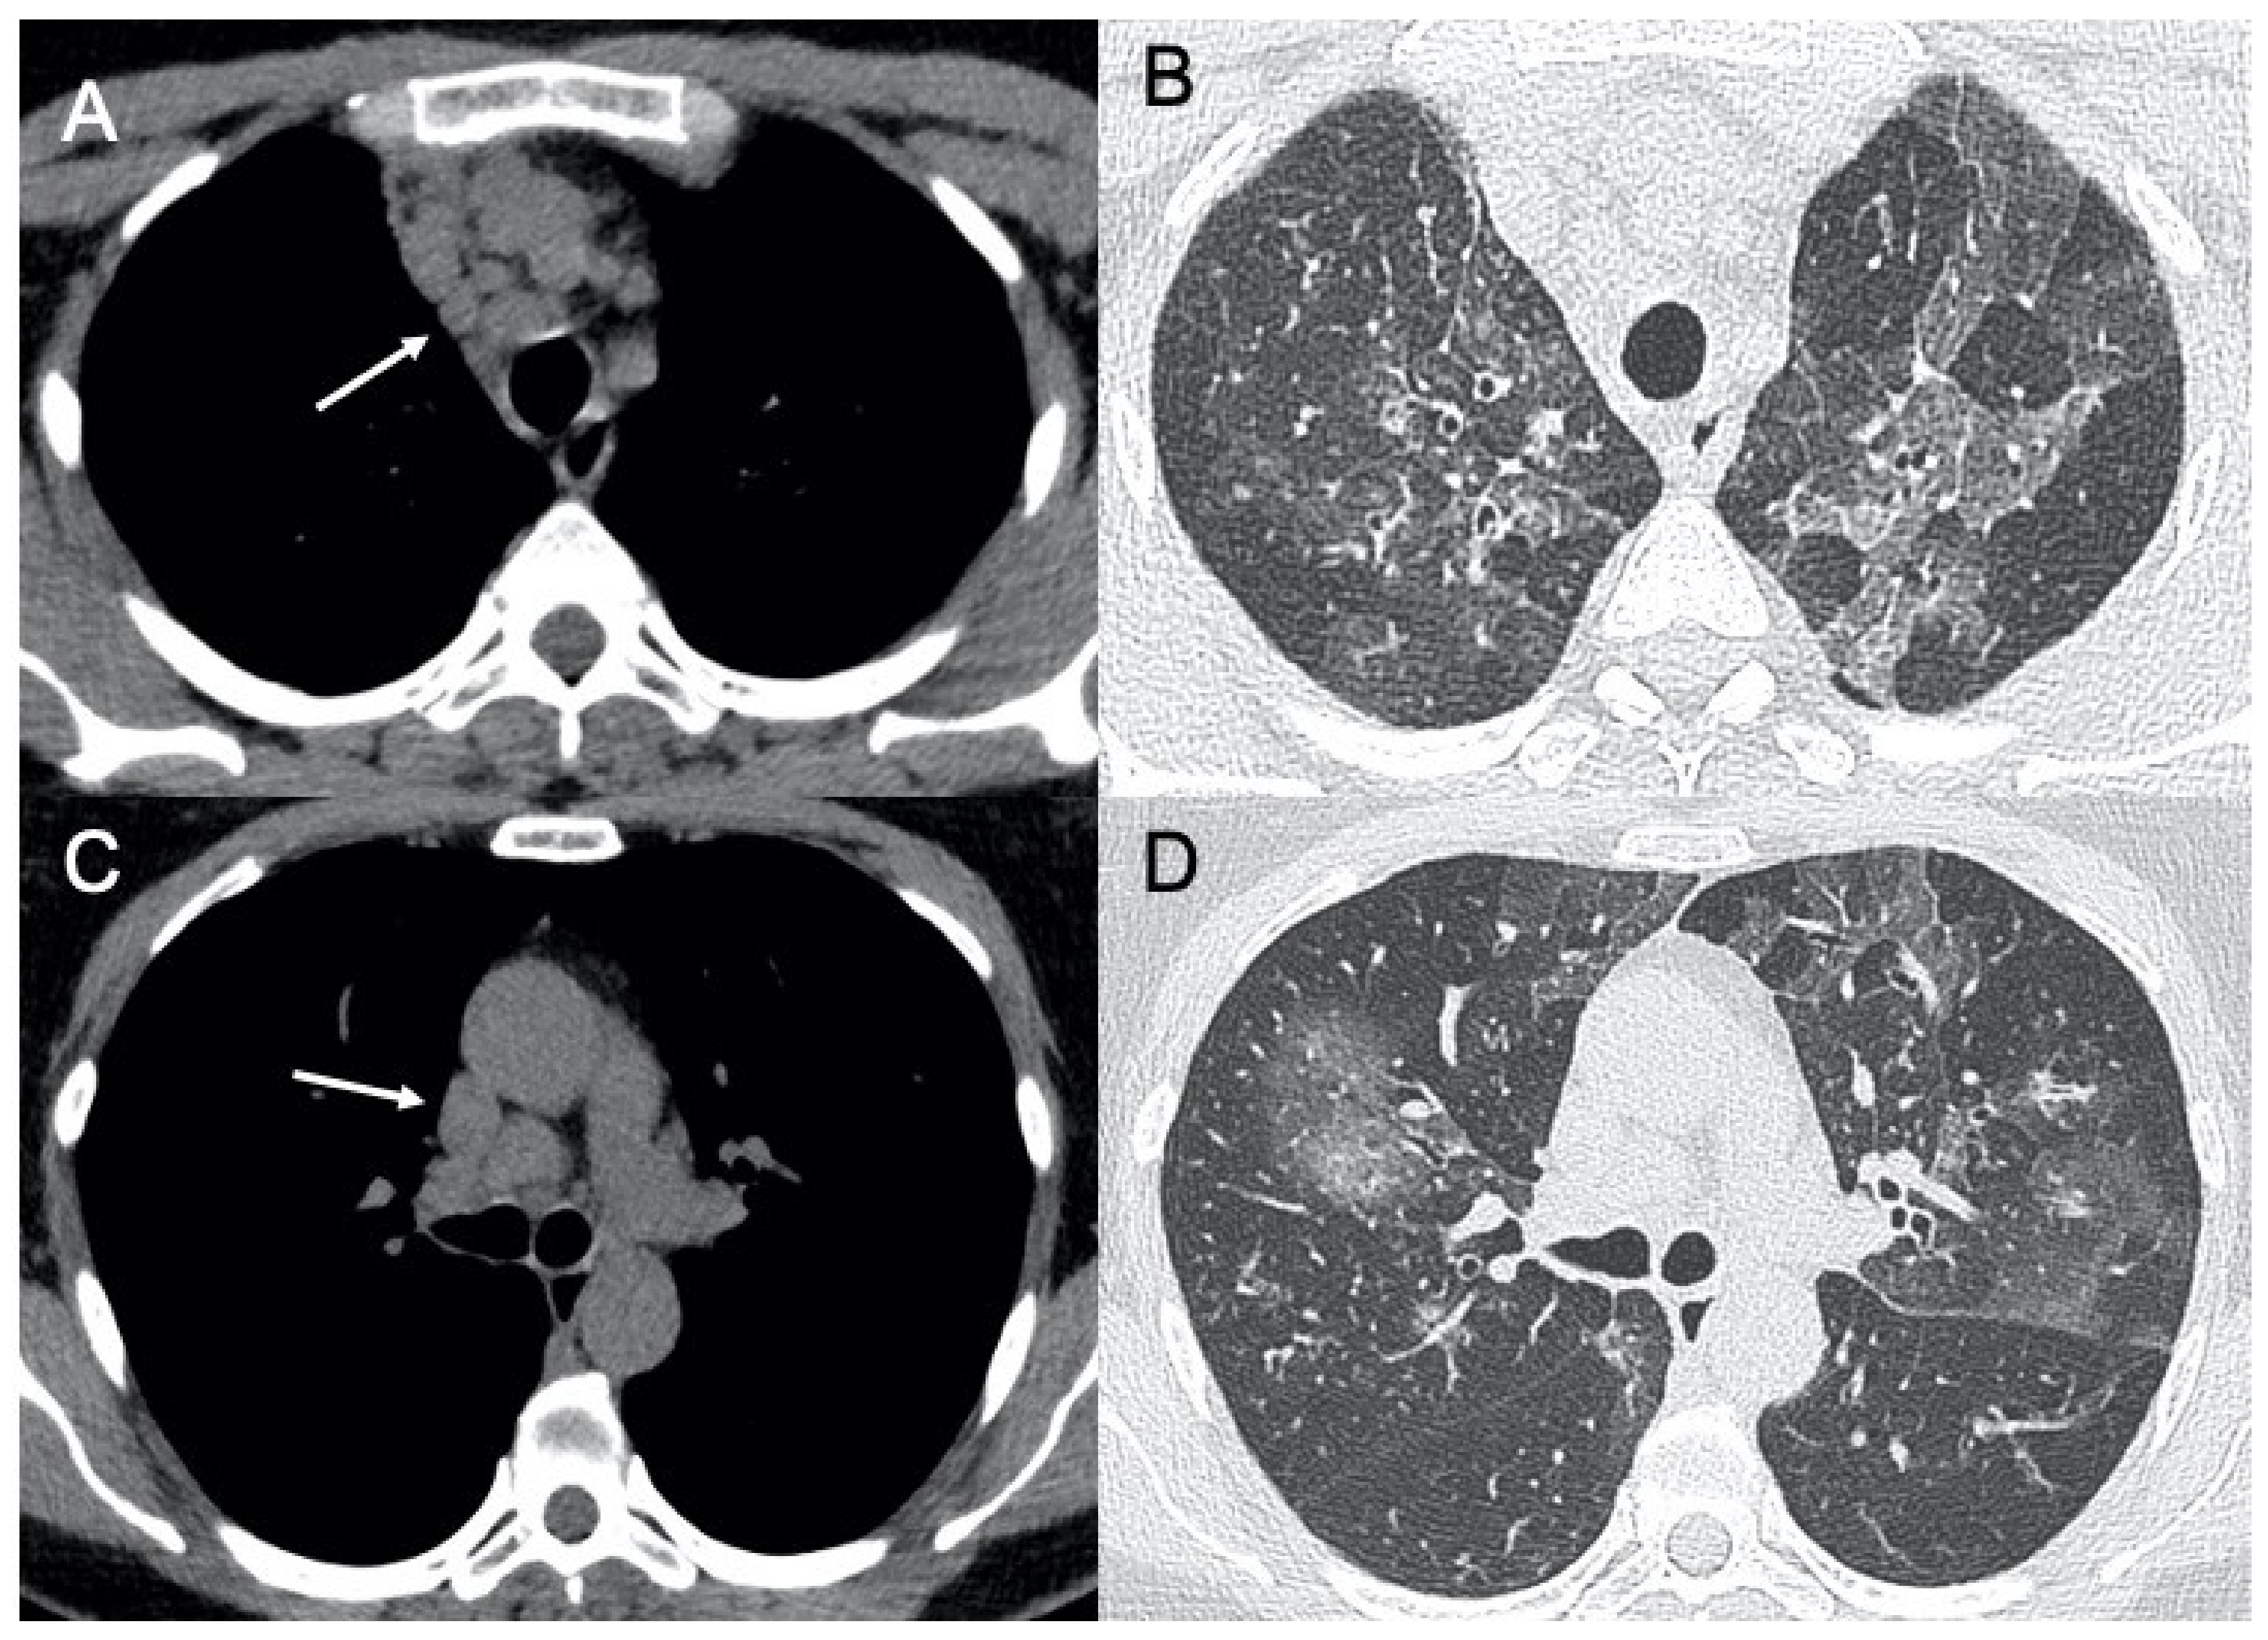

| Cytomegalovirus | Diffuse and bilateral consolidations with interstitial involvement. | Interstitial and alveolar infiltrates, bilateral and asymmetric GGO areas in association with areas of parenchymal consolidation | Figure 8 |

| Virus | Chest X-ray Signs | Chest CT Signs | Figure in the Text |

|---|---|---|---|